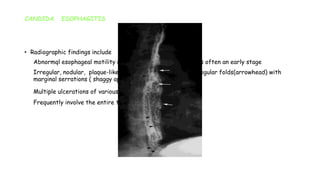

CANDIDA ESOPHAGITIS

• Radiographic findings include

1. Abnormql esophageal motility ( dilated, atonic esophagus ) is often an early stage

2. Irregular, nodular, plaque-like mucosal pattern ( arrow), irregular folds(arrowhead) with

marginal serrations ( shaggy appearance )

3. Multiple ulcerations of various sizes

4. Frequently involve the entire thoracic esophagus

CANDIDA ESOPHAGITIS • Radiographicfindings include 1. Abnormql esophageal motility ( dilated, atonic esophagus ) is often an early stage 2. Irregular, nodular, plaque-like mucosal pattern ( arrow), irregular folds(arrowhead) with marginal serrations ( shaggy appearance ) 3. Multiple ulcerations of various sizes 4. Frequently involve the entire thoracic esophagus